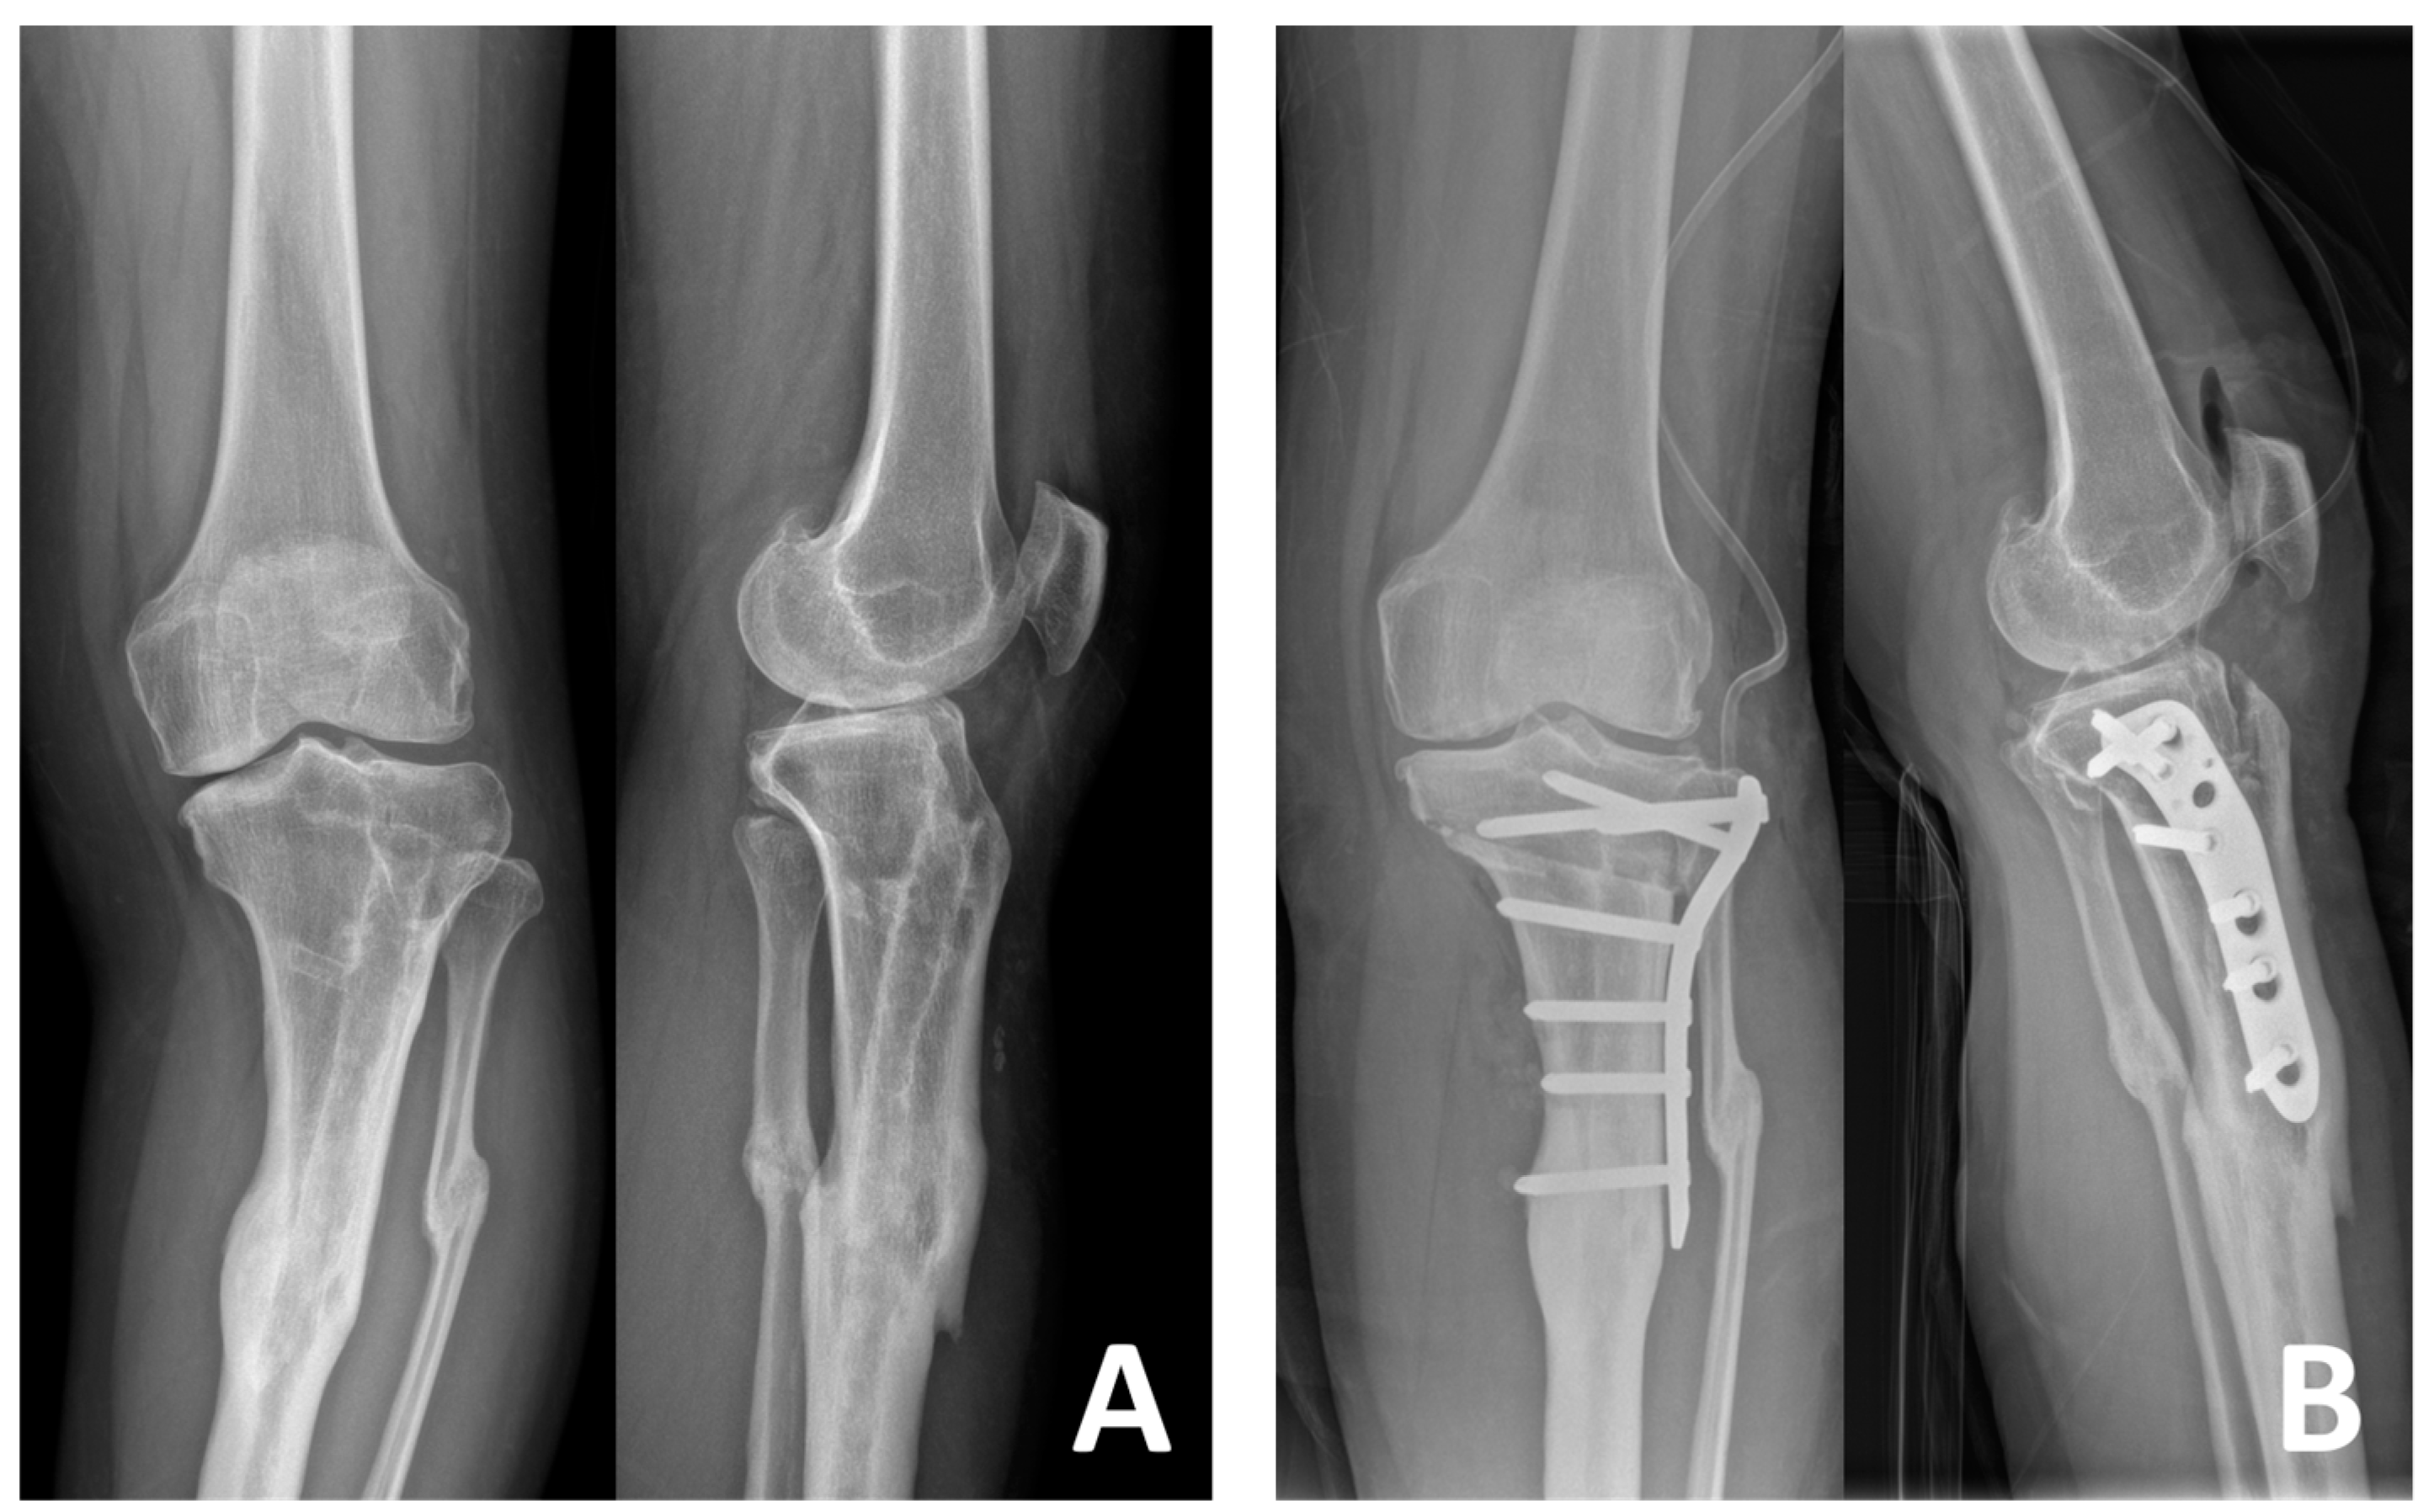

Figure 3. Preoperative (A) and postoperative (B) radiographs of a 42-year-old female patient who underwent LCWHTO using the TSO technique. LCWHTO: lateral close-wedge high tibial osteotomy; TSO: tibial-sided osteotomy.